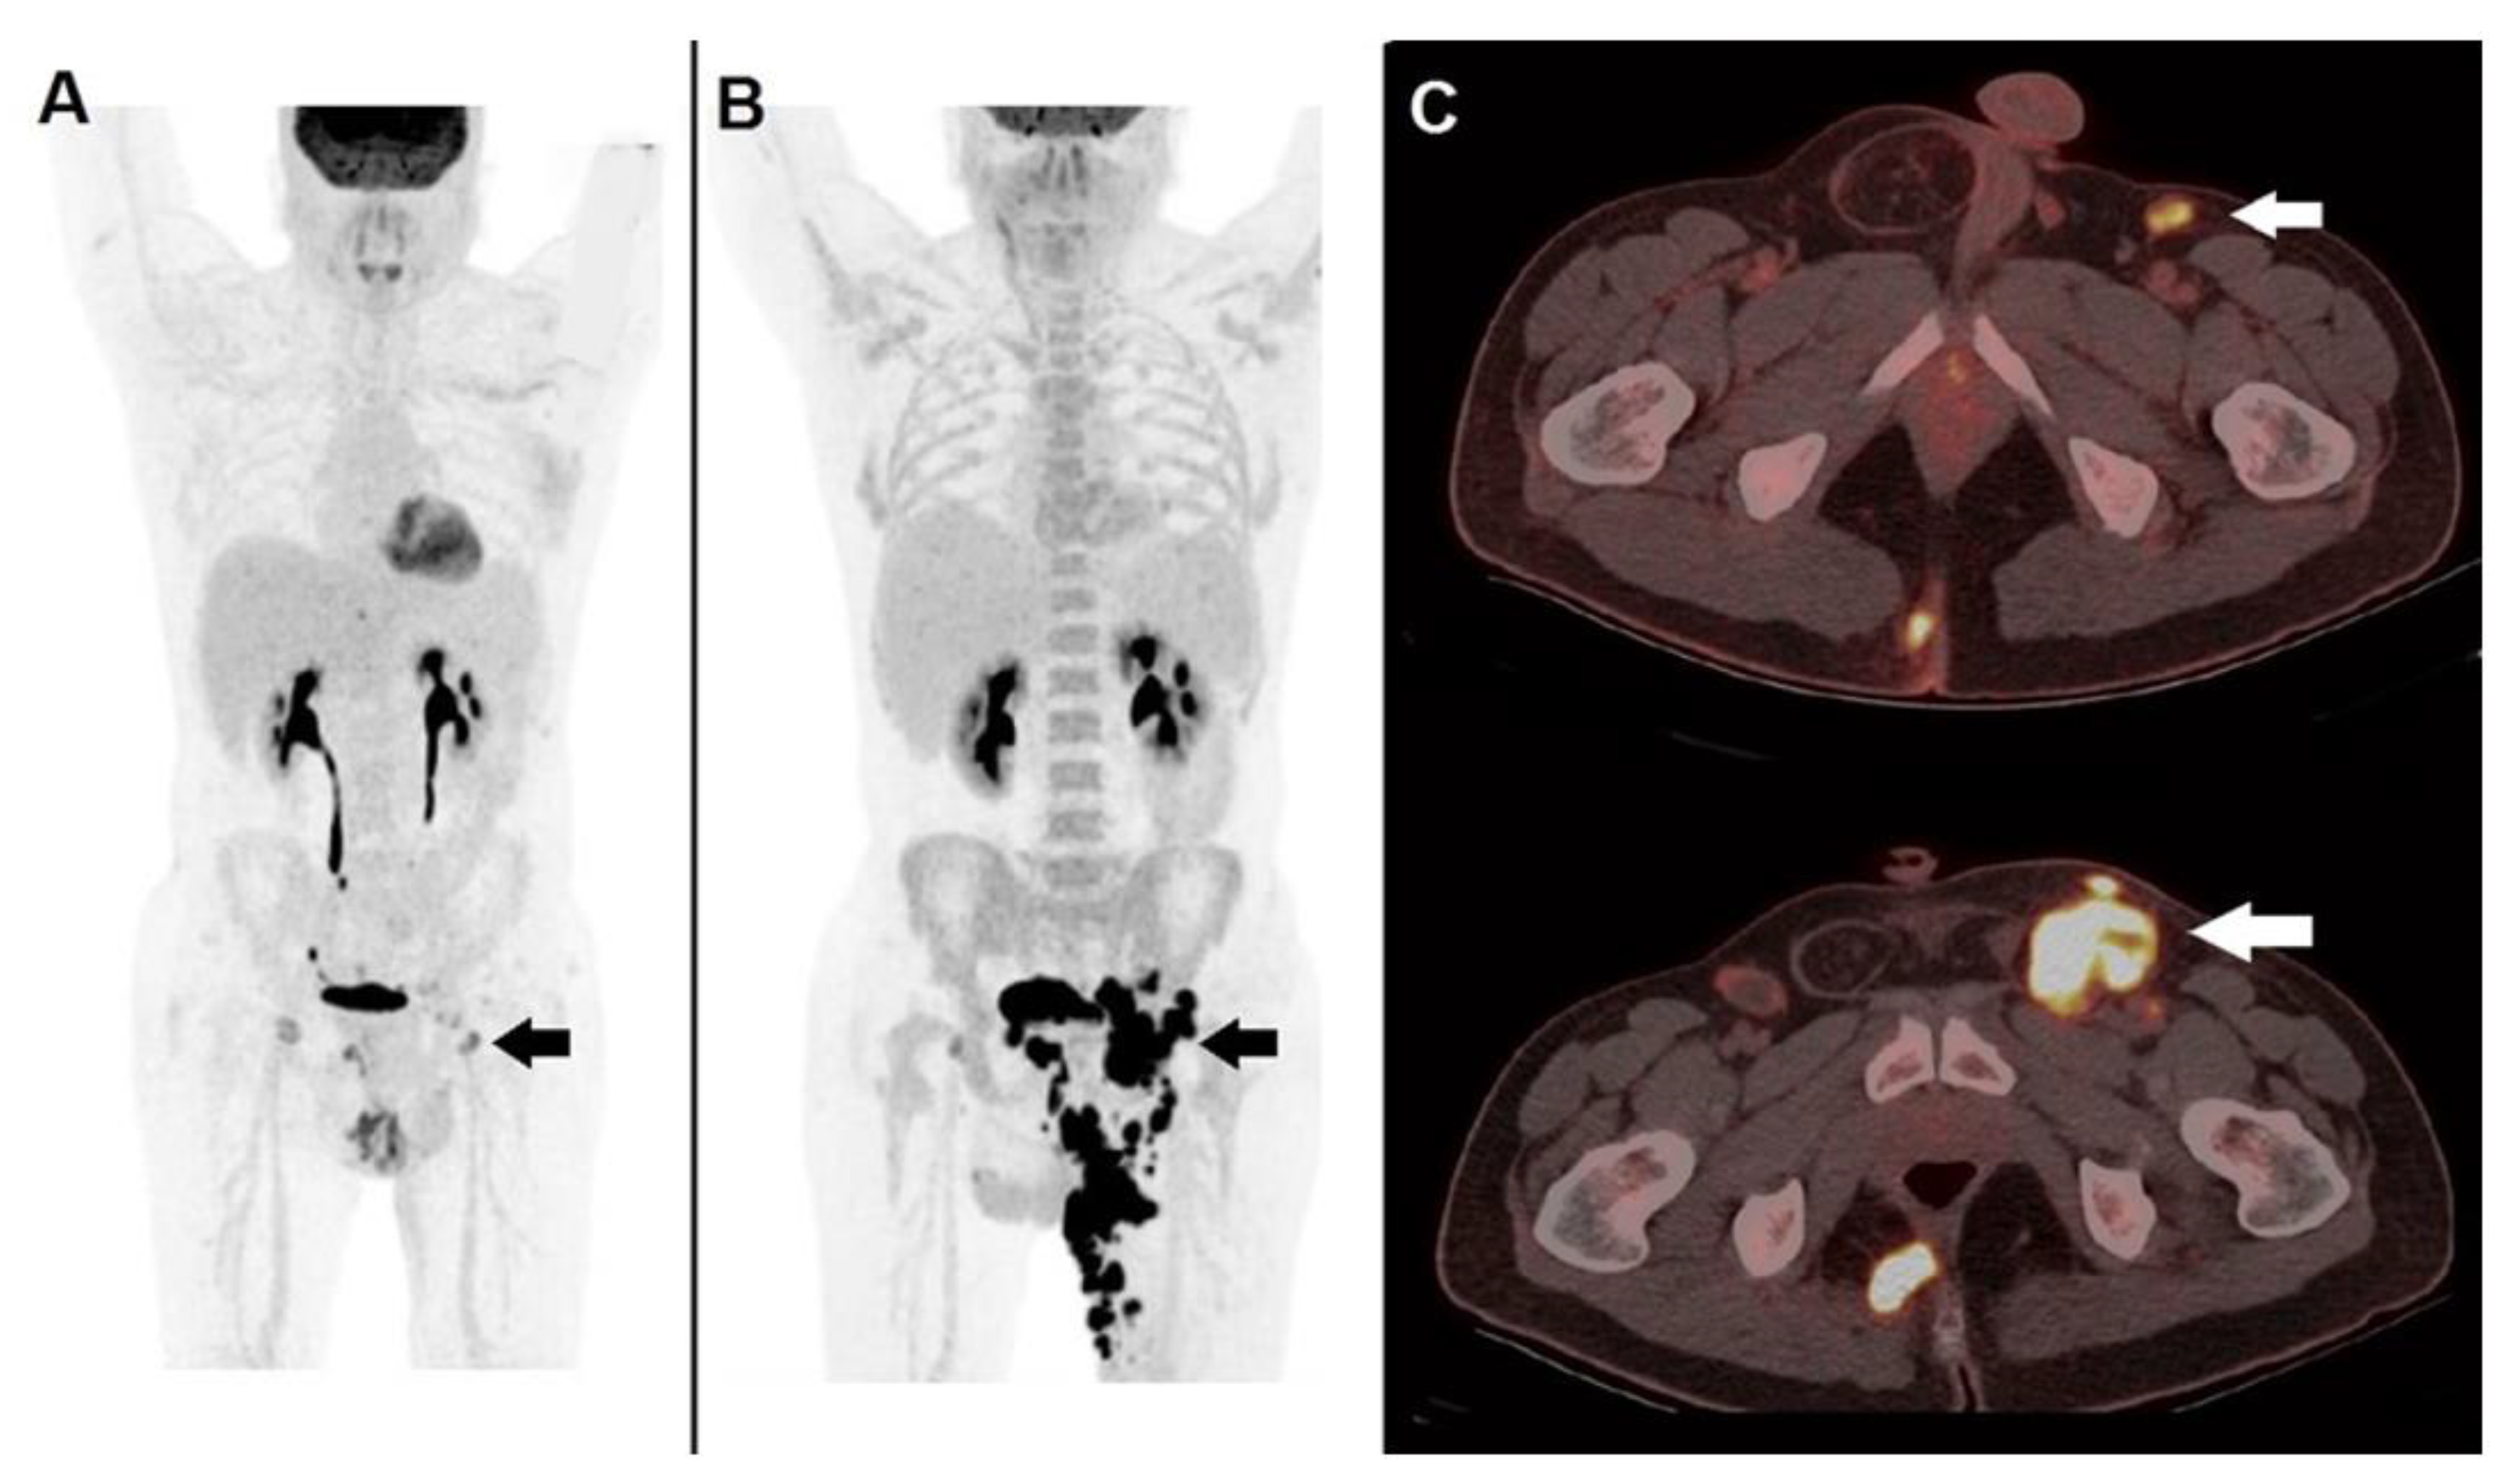

3.2. Immunotherapy: The Need for Novel Criteria

- Anwar, H.; Sachpekidis, C.; Winkler, J.; Kopp-Schneider, A.; Haberkorn, U.; Hassel, J.C.; Dimitrakopoulou-Strauss, A. Absolute Number of New Lesions on 18F-FDG PET/CT Is More Predictive of Clinical Response than SUV Changes in Metastatic Melanoma Patients Receiving Ipilimumab. Eur. J. Nucl Med. Mol. Imaging 2018, 45, 376–383. [Google Scholar] [CrossRef]